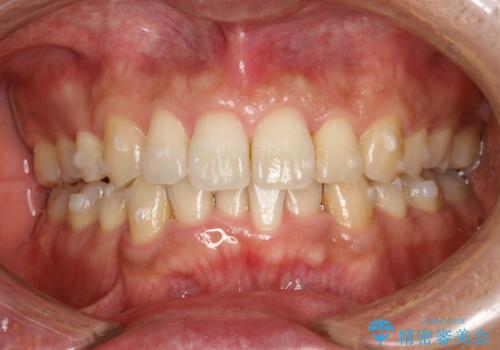

- 以前、上下左右4本抜いてワイヤー矯正をしていた方で、後戻りで下の前歯のガタガタを気にして来院されました。

マウスピース矯正にて、下の歯はIPR(歯と歯の間を削る)を入れることでガタガタの改善、咬み合わせの深さも改善をはかる治療計画をたてました。

歯と歯の間を削って隙間を作って矯正をしています。